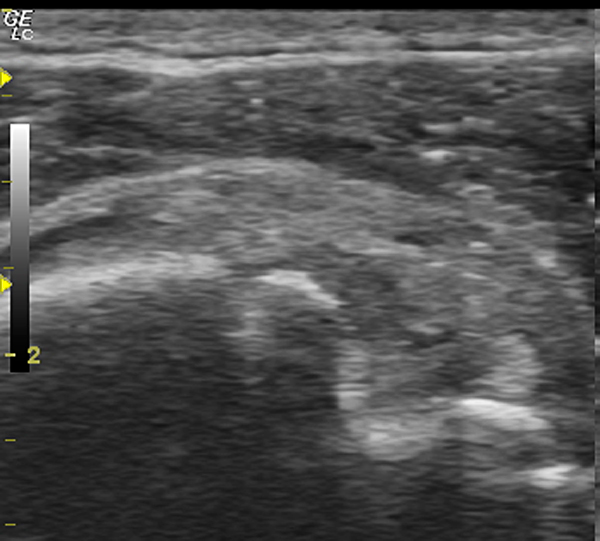

Мужчина 48 лет, нес сварочный аппарат весом под 30 кг, споткнулся и упал на плече.

После 2 недель хождений по разным врачам, различного противовоспалительного лечения, пришел на УЗИ плечевого сустава.

И вот такая уз-картина предстала перед моим взором.

На представленных сонограммах сканирована головка плечевой кости с ротаторной манжетой.